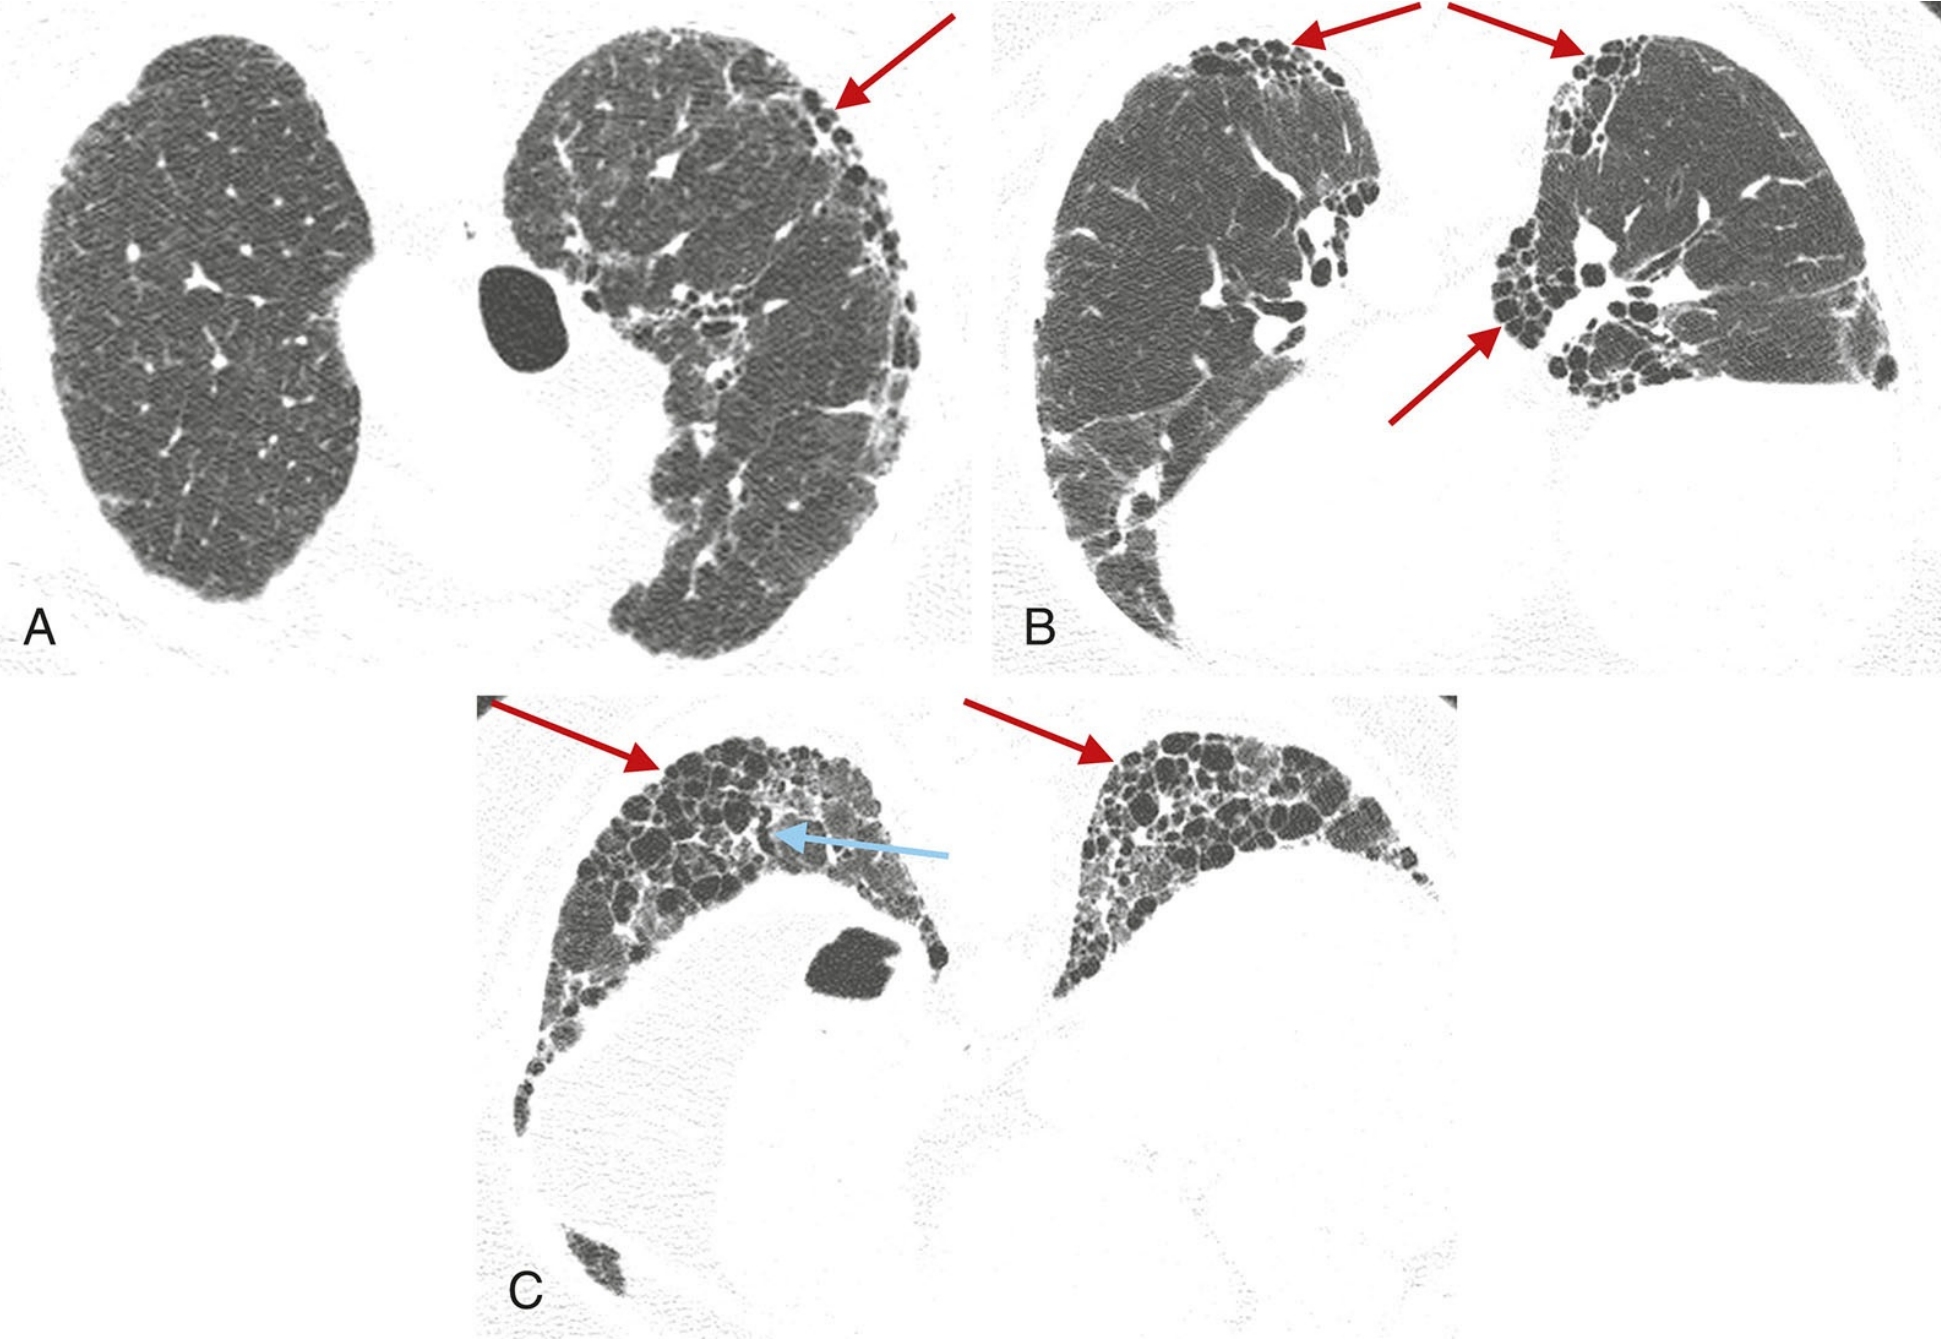

普通型间质性肺炎(UIP)的典型表现。

A.伴有特发性肺纤维化的UIP模式患者,HRCT显示广泛的胸膜下和肺基底分布为主的蜂窝征;

B.散在分布的胸膜下蜂窝征(红箭),与相对正常的肺组织(蓝箭)相间;

C.俯卧位HRCT显示UIP患者的蜂窝征(箭),可为单层(黄箭)或多层(蓝箭);

D.早期UIP表现为轻度的胸膜下网状影和蜂窝征,虽然程度轻微,但仍可明确判定蜂窝征(箭)。